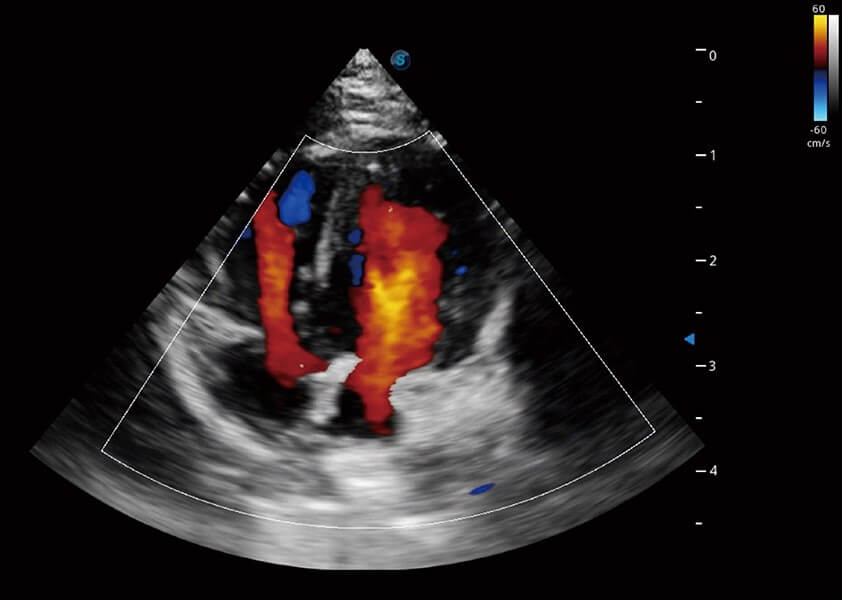

心脏解决方案

ProPet 60 配备了丰富的心脏探头群、先进的成像技术和专业的心脏测量工具,可帮助动物医生为不同体型和生理结构的动物提供心脏和心肌功能的全面评估。

• TDI 组织多普勒成像

实时用颜色表示心肌组织运动,观察和定量组织的运动情况,对快速检测与评估心肌的灌注和活性、电传导及心肌收缩和舒张功能等均能提供重要的诊断信息。

优异的基础图像

(犬)四腔心血流

(犬)心脏组织多普勒